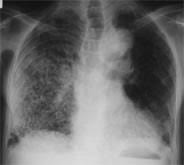

(1) 흉부 X선 촬영

① 폐결핵이 의심되는 경우, 가장 먼저 시행되는 검사입니다.

② 활동성 결핵은 폐의 상부 엽에서 공기 음영 및 공동 형성을 보입니다.